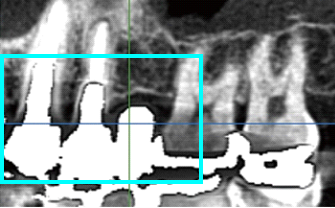

BioNaシミュレーション画像

BioNaシミュレーション画像 歯牙支持型フラップレス

歯牙支持型フラップレス